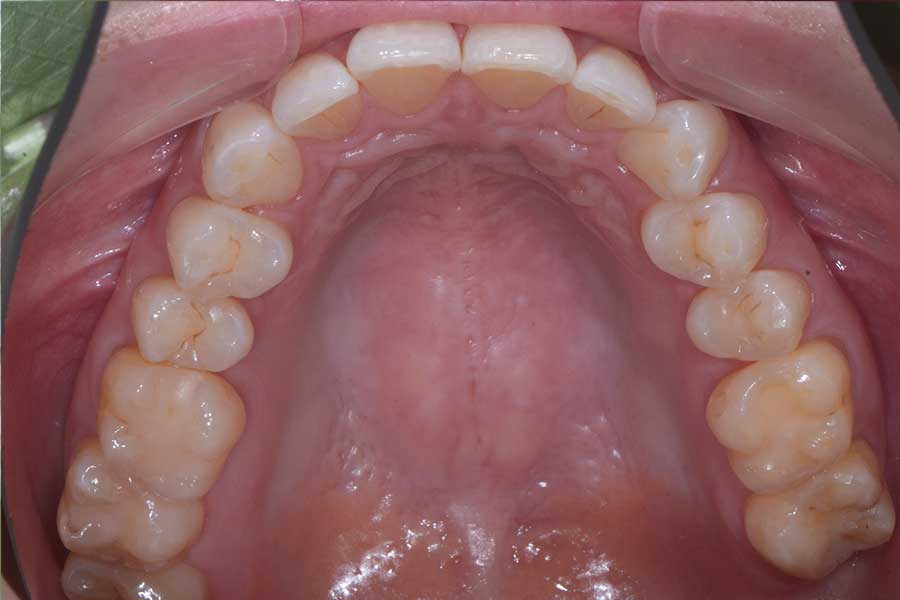

治療後

主訴 インプラント治療前にブラックトライアングルを消したい

治療内容 上下顎ラビアル矯正(表側矯正)